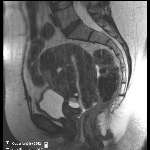

| Arterial phase & portal venous phase | |

![]()

| ![]()

|

| |